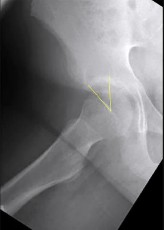

A 38-year-old male presents with right hip pain. He has a history of long-term corticosteroid use for severe asthma. Radiographs demonstrate an area of sclerosis and subchondral radiolucency (crescent sign) in the anterosuperior aspect of the femoral head, consistent with osteonecrosis. According to the modified Ficat and Arlet classification, the presence of a structural subchondral collapse (crescent sign) without narrowing of the hip joint space places him in which stage?

The Ficat and Arlet classification is classically used to stage osteonecrosis of the femoral head based on standard radiographs. Stage I has normal radiographs (but positive MRI). Stage II shows cystic/sclerotic changes without subchondral collapse. Stage III is defined by subchondral collapse, which is classically visualized as the 'crescent sign' (subchondral radiolucency indicating mechanical failure of the trabecular bone), but the joint space remains preserved. Stage IV involves secondary osteoarthritis with joint space narrowing and acetabular changes.